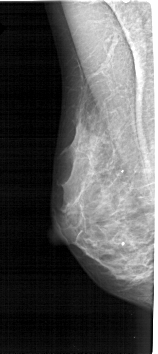

A_1272_1.LEFT_MLO

LEFT_MLO LINES 5296 PIXELS_PER_LINE 2356 BITS_PER_PIXEL 12 RESOLUTION 43.5 NON_OVERLAY